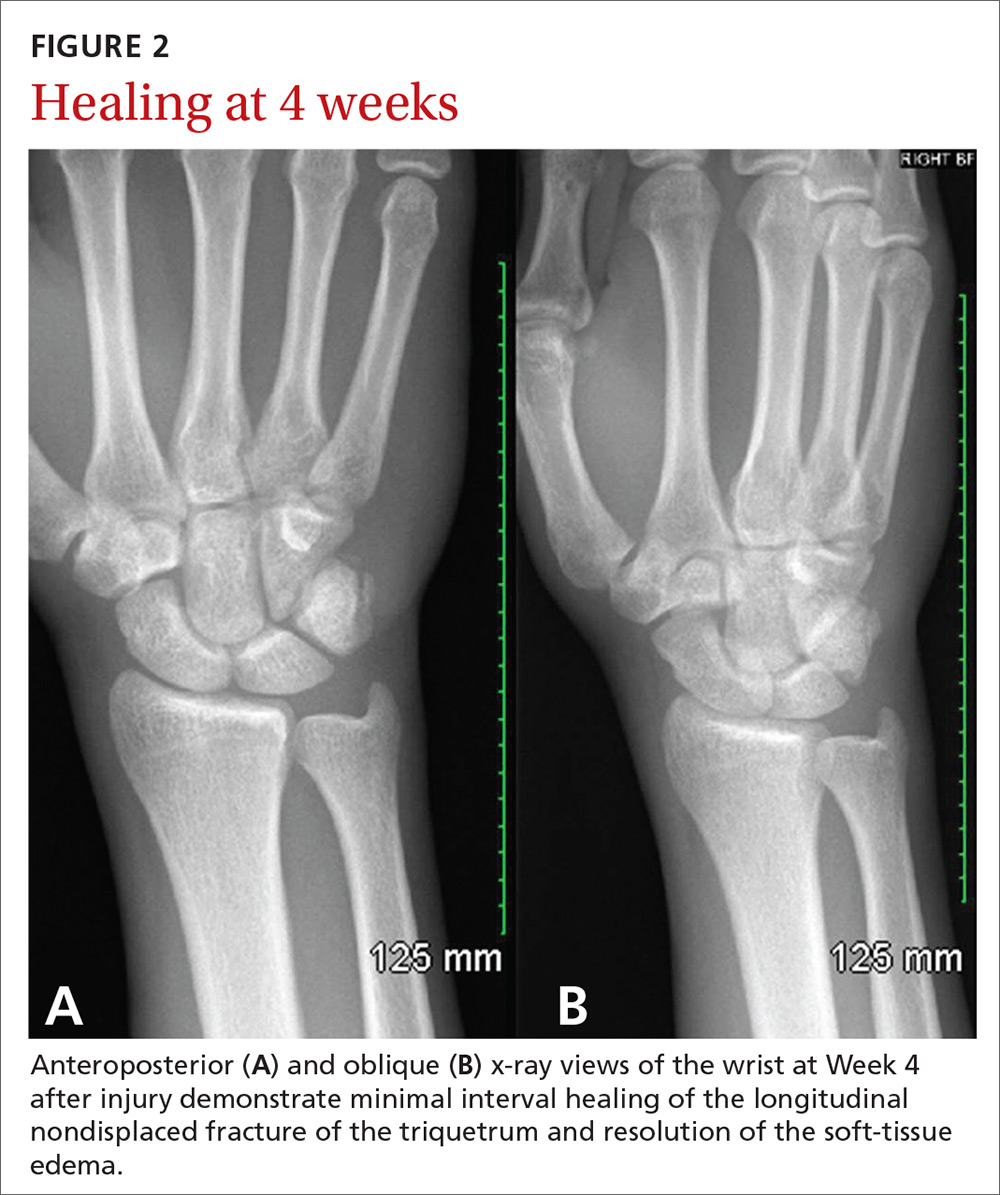

Triquetrum Fracture X Ray Diagnosis is confirmed with orthogonal views of the wrist. Triquetrum fractures typically occur from a fall onto an outstretched arm with the wrist in extension and ulnar deviation, or in extreme. Diagnosis is confirmed with orthogonal views of the wrist. Triquetral fracture is carpal bone fracture that generally occurs on the dorsal surface of the triquetrum. Triquetral fractures are the most common carpal fracture after scaphoid fractures. Triquetrum fractures are common carpal fractures that are often associated with other injuries to the wrist. A triquetrum with a normal appearance. Although they are usually managed. It may be fractured by means of.

From casereports.bmj.com

Simultaneous bilateral triquetral fractures, acquired in two separate Triquetrum Fracture X Ray Diagnosis is confirmed with orthogonal views of the wrist. Triquetral fractures are the most common carpal fracture after scaphoid fractures. It may be fractured by means of. A triquetrum with a normal appearance. Triquetrum fractures typically occur from a fall onto an outstretched arm with the wrist in extension and ulnar deviation, or in extreme. Although they are usually managed.. Triquetrum Fracture X Ray.